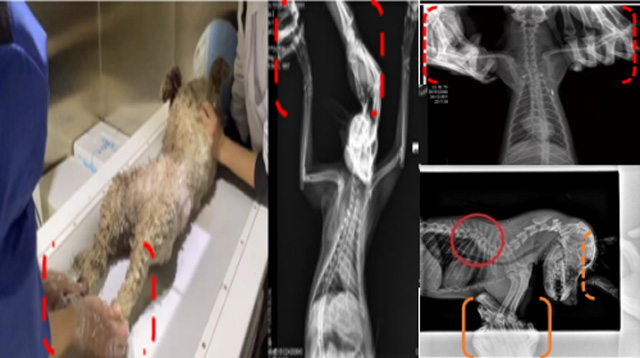

现在宠物医疗设备得到高速发展,现在有越来越多的宠物诊疗机构配置X射线装置如宠物DR。宠物骨折或者有其他疾病不能通过直观看出来的。宠物诊所医生都会使用宠物DR来做辅助检查。但是有时候宠物医生没有加强防护,就在宠物DR室给宠物拍X片做检查。这样也是会受到X射线的辐射。因为X射线上岗是属于职业病危害岗位。长期的辐射会对人体造成一定的危害。宠物医生也需要接受X射线照射的上岗前都必须进行放射工作人员的职业健康体检。体检不合格的话是不能担任放射工作的。未经上岗前职业健康体检的劳动者从事接触职业病危害作业的行为,已经违反了《中华人民共和国职业病防治法》第三十五条规定,依据《中华人民共和国职业病防治法》第七十五条规定,需要进行整改??睢?钩栉锓派湔锪苹疃谌粘9ぷ髦?,对本机构的X射线危害的职业病防治,需要知道并做到以下内容:

建造X射线机房时寻找专业防护施工队伍,对机房四方及上下方墙体进行屏蔽防护,尽可能隔室操作,使用铅防护门并安装工作指示灯张贴警示标识进行提醒。放射工作人员跟宠物主进入DR室需要穿戴铅衣、铅帽、铅手套等做好防护,减少X射线的辐射。避免暴露在照射范围中。宠物医生上岗前、在岗时、离开岗位时候的职业健康体检。如果检查异常就需要复查跟调离放射岗位。实施个人剂量监测和防护知识培训。并在劳动合同中向放射工作人员告知X射线危害相关内容。定期委托职业技术服务机构对机房防护、放射诊疗设备性能进行检测。不能忽略了对人的?;?。